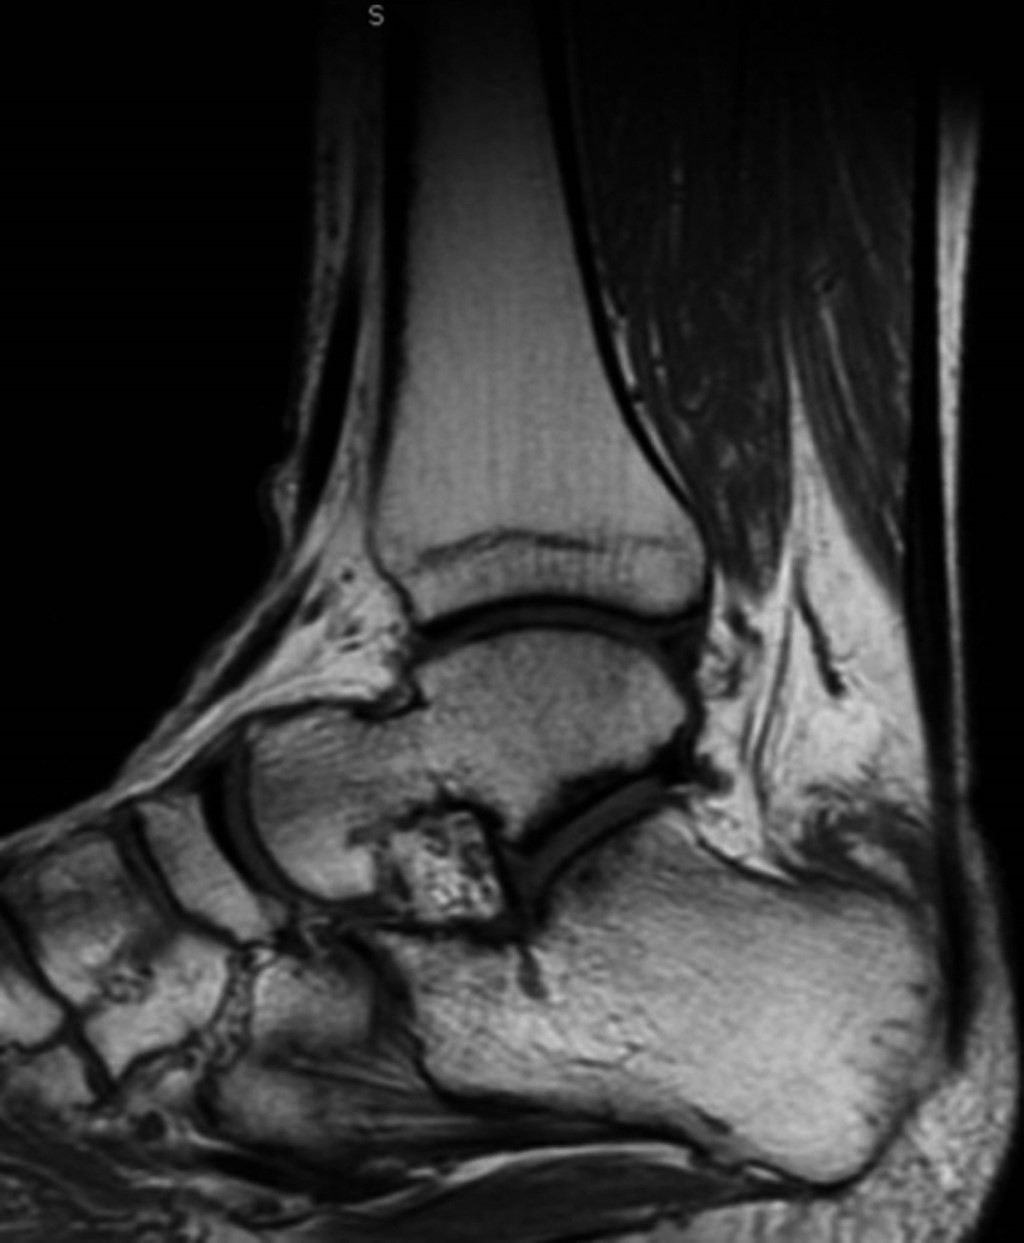

En nuestra primera consulta se envió a terapia física y rehabilitación realizando un total de ocho sesiones dentro de nuestra institución, no mostrando mejoría ni disminución del dolor, por lo que se solicitaron estudios de imagen, los cuales consistieron en radiografía anteroposterior y lateral de tobillo en la cual se evidenció adecuada congruencia de la articulación tibioastragalina y tibioperonea, exostosis posterosuperior de calcáneo de 6 milímetros de altura con relación a la línea articular superior, y alteraciones en la grasa de Kager (Figuras 1 y 2). De igual manera, se realizó resonancia magnética de tobillo evidenciando tendinitis aquílea, bursitis retrocalcánea y líquido en la bursa retroaquílea de aproximadamente 3 cm3. Se observa tendón aquíleo engrosado en su inserción y tendinitis insercional con edema óseo en región posterior de calcáneo (Figura 3).

Figura 3